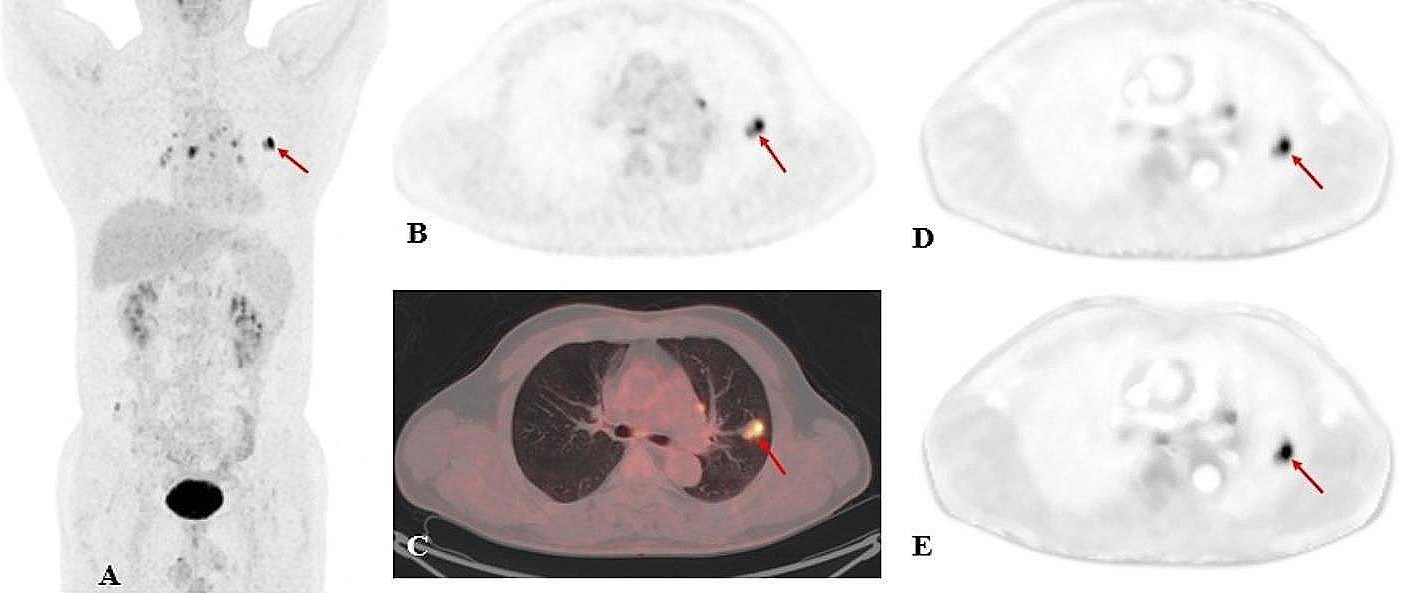

A case example of a 63-year-old patient with esophageal cancer. FAPI-46 PET/CT was performed for irradiation planning before definitive radiochemotherapy. FAPI-46 PET was performed 10 minutes, one hour, and three hours after injection. Image courtesy of the Journal of Nuclear Medicine.The FAPI-PET scans revealed 171 lesions in the 43 patients. Comparing all lesions at different time points, the mean SUVmax was maximal at 10 minutes (8.2) and declined slightly at one hour (8.15) and at three hours (7.6) after tracer administration, the team found.

Additionally, the mean SUVmax had a similar pattern in primary lesions, lymph node metastases, and distant metastases. TBRs also showed nonsignificant differences at the three times.